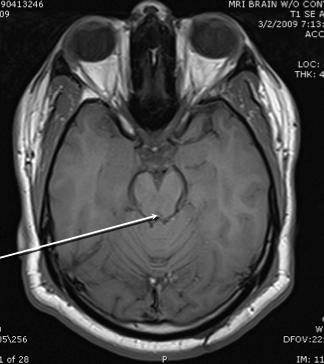

crus cereberi

hypothalamus

cerebral aqueduct

cerebellum